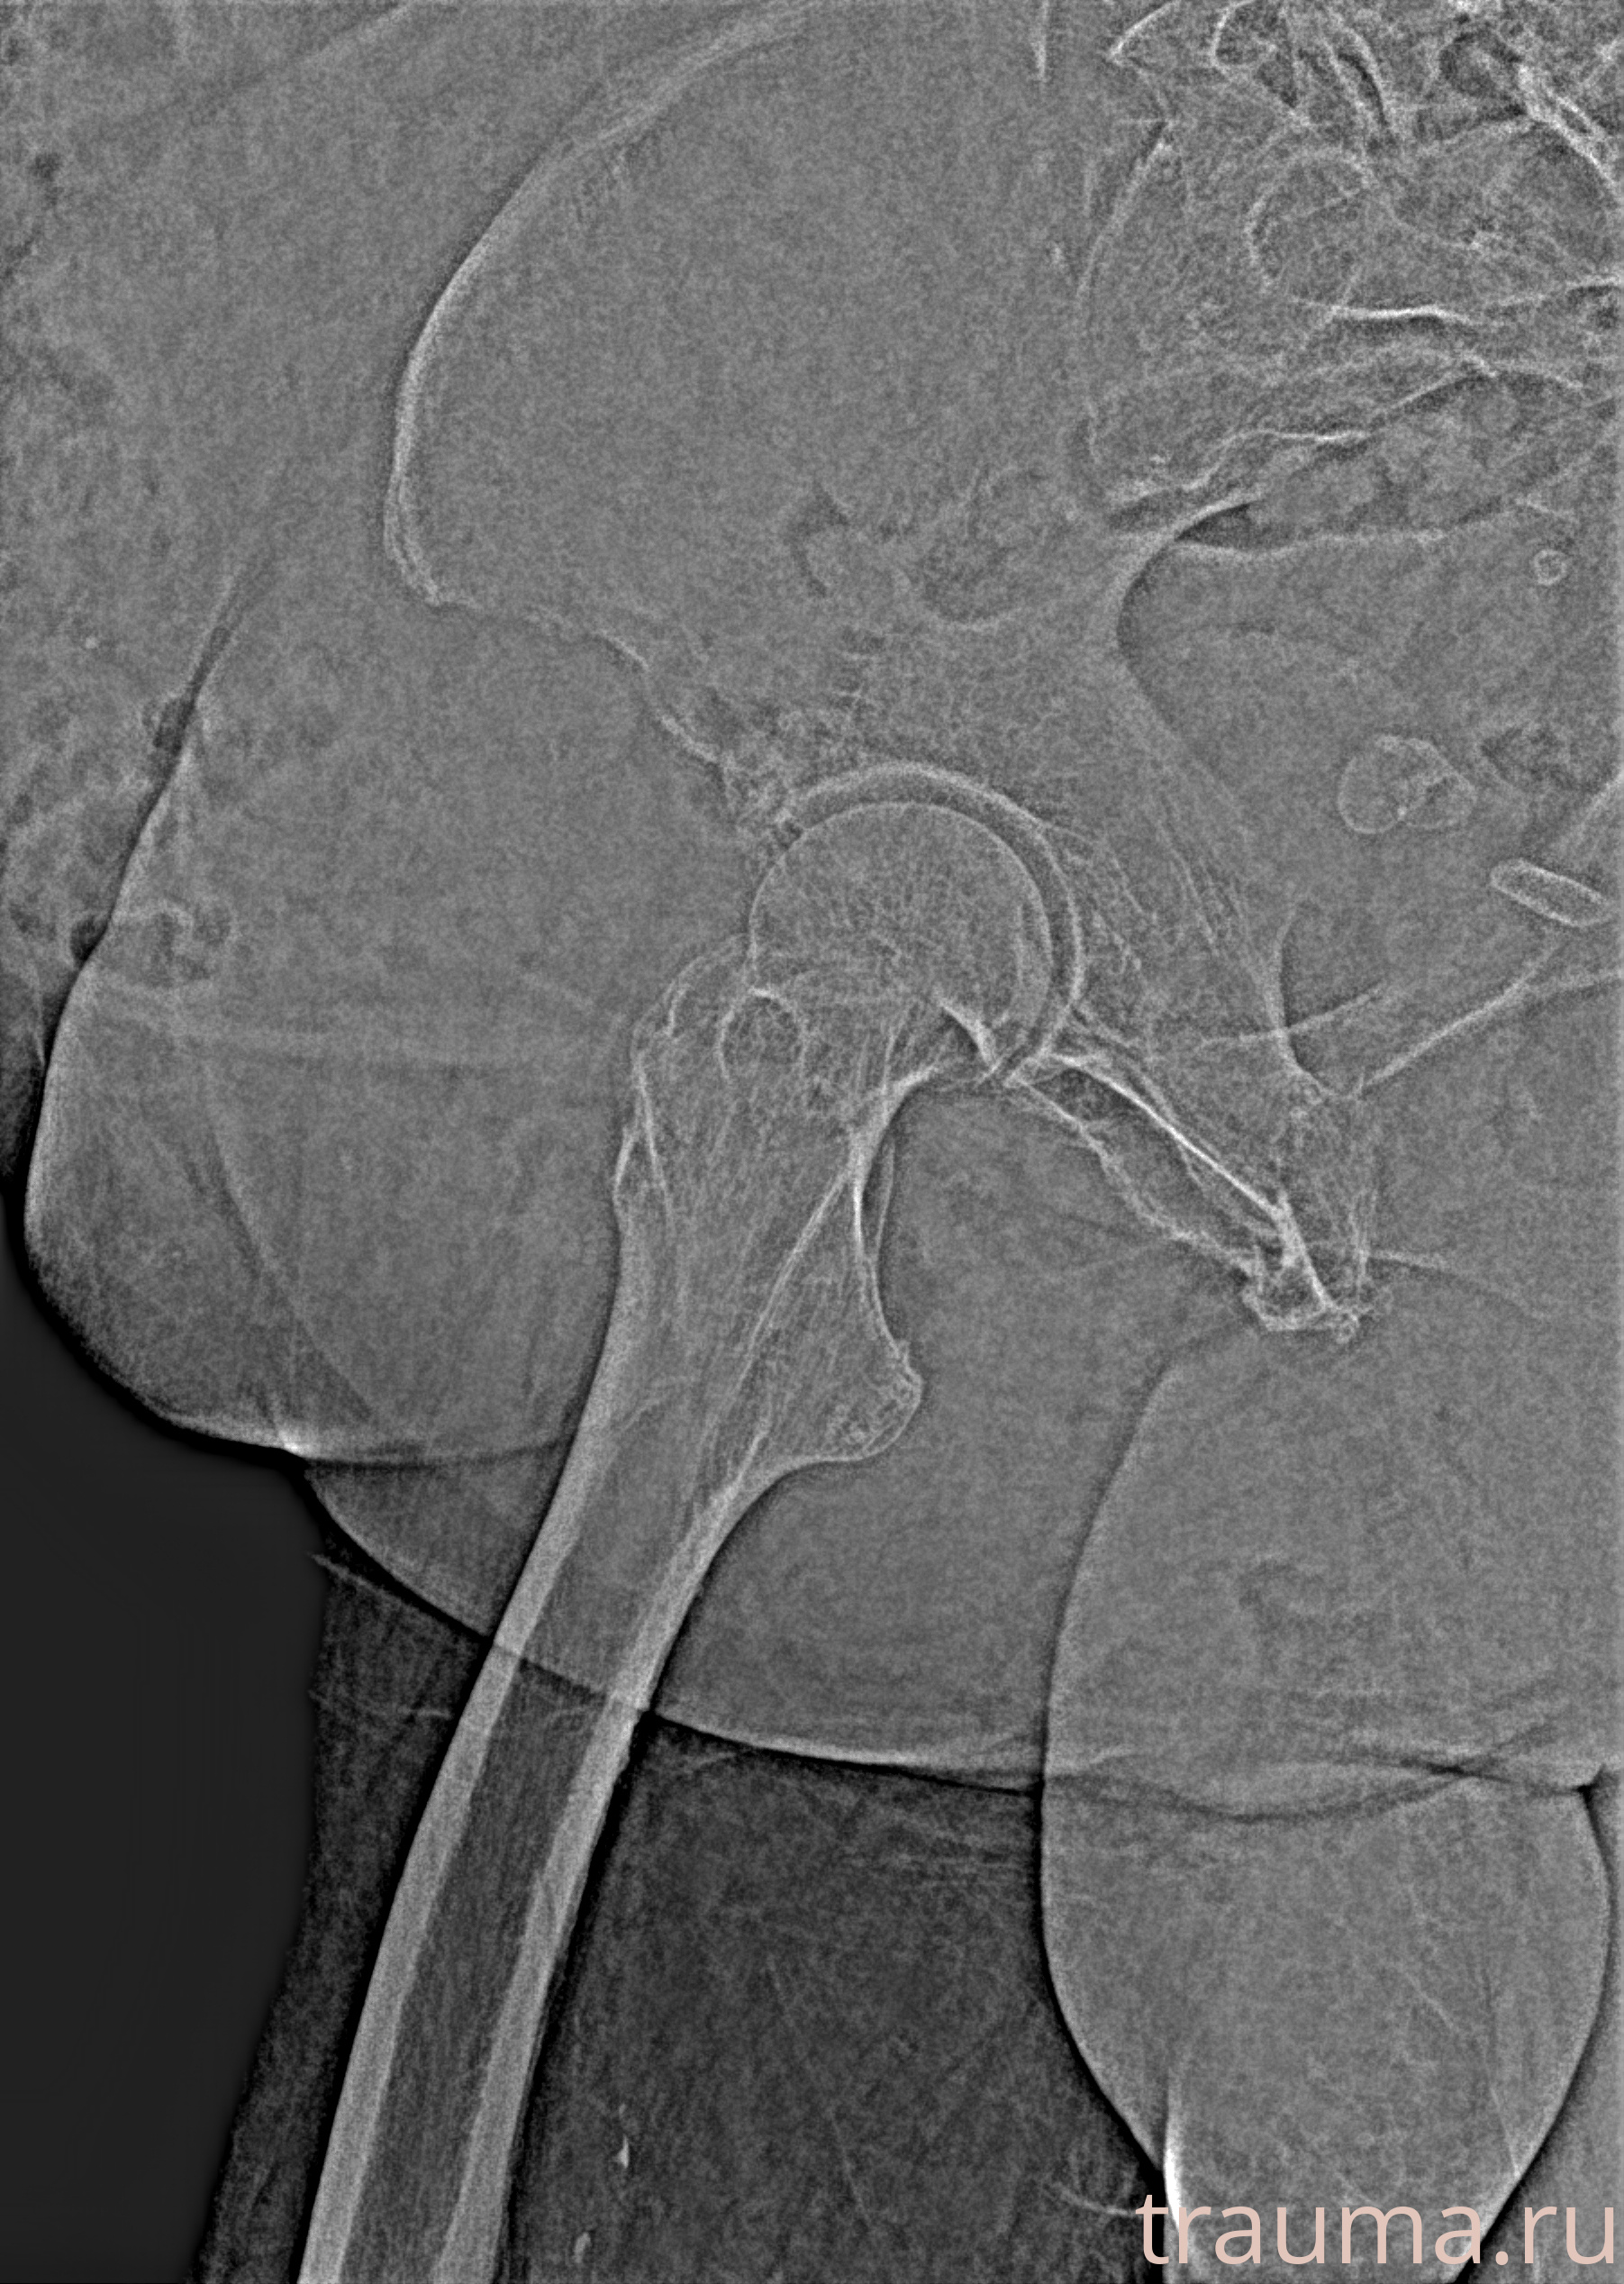

Рентгенограммы

Рентген на дому: по вашему адресу приезжает врач-рентгенолог, травматолог-ортопед с мобильным рентгеновским аппаратом, проводит диагностику травмы или заболевания, делает необходимые рентгенограммы, дает рекомендации по дальнейшему лечению. Получить качественные снимки в домашних условиях возможно благодаря уникальной методике, разработанной МосРентген Центром для института  Склифосовского